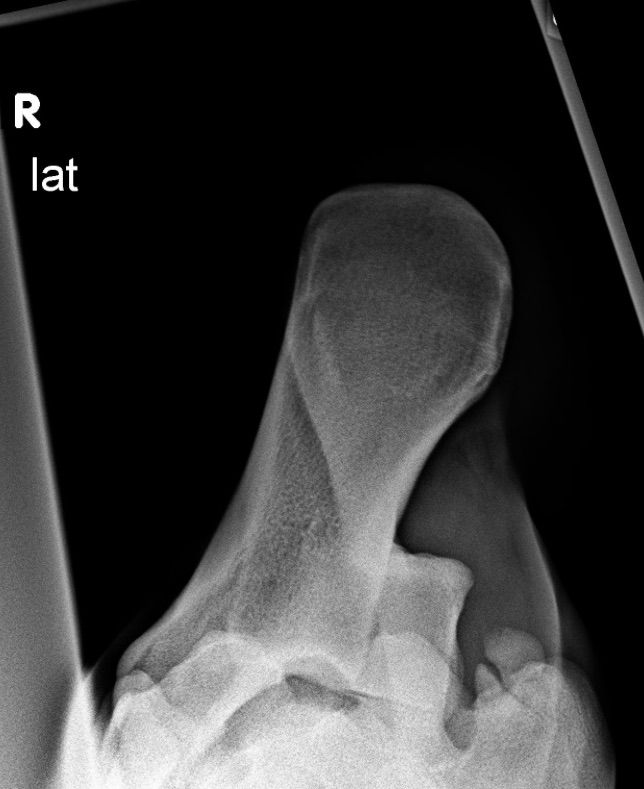

| Dire merci | Retour du veto. Alors. On a commencé en ligne droite sur le dur puis cercle Rien de franc. Pareil dans le manège. Il trottait même plutot bien d'ailleurs. Le pied droit traîne un peu mais elle disait que vu que la hanche droite " tombe" toujours un peu Ca n'a rien de vraiment anormal. Tests de flexion pareil. Rien .,., Du coup elle me dit que c'est as assez net pour un diagnostic Ét que peut être au final le jarret a bougé. J'lui dis que c'est ce à quoi je pensais. Donc on passe aux radios. La vie habituelle est la meme. Du coup elle ajoute un cliché vu d'en haut. L'aide prend un peu le jarret pour avoir une petite flexion et photo. Et donc elle m'emmène dans son bureau pour me montrer le comparatif 2013-ce jour. Premier cliché rien. Pas de différence. 2eme un écart bien plus important d'une fissure. J'ai pas pigé la fissure car je croyais que le bout d'os était deja détaché.... Truc assez rare A priori pour qu elle ai des bouquins ouverts à côté sur ce type de truc.... ( avec pas grand chose DE noté lol ) En anglais en allemand ... |

Par zenzile : le 12/05/16 à 19:07:07

| Dire merci | Du coup elle parle boiterie franche, opération, nécessite d'un scanner avant op. La j me dis bordel si..... J'pourrai pas le payer sans me foutre en dettes vu que le changement de boulot me met assez dans la merde depuis 2 ans... Elle me dit à ma place elle opérerait pas encore, mais qu'elle va contacter un spécialiste de ce genre de trucs pour lui montrer, avoir un avis juste qu'on puisse se demander " qu'est ce qu'on peut faire au cas où" ét ne pas regretter d'avoir pas eu de solutions au cas où. 'Sachant que les chevaux qu'elle a vu (?2 ou 3) avec ce type de truc, l'op ne les a pas sauvé. Que la question n'est même plus d'avoir un cheval au boulot ou juste pour de la balade, que si Ca Pete ce sera " franchement ét complètement boiteux" ( DE ce que j'ai compris) |

| Dire merci | Que la maintenant tout de suite il ne boîte pas. Donc il FAUT qu il bosse. Il faut du muscle.( qui m'arrangerai si j'avais pas tjs ces soucis de poids ). Ensuite il a vu la chiro quand même ! Elle a réussi à me la faire venir, m'a prêté un box le temps qu'elle arrive. Côté chiro raideur sacrum qui esr complètement normale et compensatoire du jarret et sera toujours à faire manipuler. Les premières cervicales ( Ca j'avais remarqué ) Puis le début du dos sous le pommeau à faire monter ( qui S est affaissé quand il a perdu ses kilos ) Donc : encore une semaine de repos puis reprise du boulot avec beaucoup de cavalettis et dans position horizontale / vers le bas surtout. |

| Dire merci | bon... je suis en phase digestion de "nouvelles". En attendant la suite, c'est à dire, savoir ce que dira l'autre véto que la mienne contacte. J'ai demandé les clichés. Du coup de profil ca n'a ps tant bougé mais un peu, c'est plus net, et l'autre vue de "en haut" et de derrière le jarret, on voit clairement le petit bout qui s'"arrache". ![]() ![]() Donc, l'attente c'est essentiellement que je risque de ne plus pouvoir sauter au final. Donc je pense qu'on va finir notre vie sur des cavalettis. Alors au final, je ne sais pas réellement QUAND ca a pété cette histoire, c'est juste que j'avais constaté une déformation du sabot qui n'a jamais été très très beau non plus à droite derrière, et en fait mon maréchal à sa dernière visite m'a dit "oh putain ouais ça c'était pas comme ça la dernière fois, il y a eu un truc, il en a chié ou quoi" `Donc entre janvier et mars (ou février et avril je ne sais plus ) ça a bougé. Sans qu eue ne le sente vraiment, j'avais vu qu'il trainait un peu le postérieur en longe, ce qui en soi n'avait donc pas tant inquiété la véto jeudi. Mais voilà, la radio a parlé. le cheval en soi va très bien. Il a une très bonne tête, il va au pré la journée. (toute la journée voire demi journée). Et il rentre en marchant droit (aussi droit qu'il peut avec ses aplombs pourris ) Je pense, au final que j'ai acheté le cheval avec ce petit "truc" à l'origine.... on n'a jamais su d'où ça venait. Bon. Ben voilà hein ... le truc ce sera de savoir s il faut opérer ou pas, parce que le soucis, c'est que j ai vraiment plus d'argent ....... et en fait c'est "ca" qui m'emmerde le plus au final. |